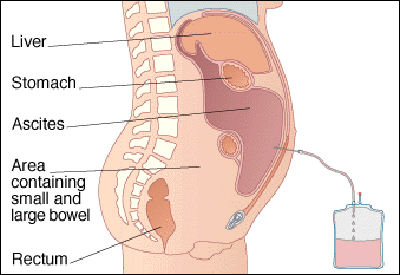

عکس داخل شکم انسان. در این همان طور که مشخص است شکم حالت بیضی شکل پیداکرده و این بیضی که کناره های شکم کشیده شده است. تعداد سلول های بدن انسان حدود ۳۷ ۲ تریلیون تخمین زده شده اند. Abdomen که در زبان عامه به غلط به آن دل نیز می گویند در آناتومی به قسمتی از تنه گفته می شود که مابین دیافراگم از بالا و سطح فوقانی لگن خاصره از پایین قرار دارد. ربات دیدنی ربات انساننمای چینی به صورت یک دختر جوان ساخته شده و جیا جیا نامگذاری شده است این ربات طوری برنامهریزی شده که میتواند صحبت کند و احساسات خود را از طریق تغییرات در چهره حالات.

شکل دوم شکم مادری را نشان می دهد که جنین دختر دارد. وحشت مادر از عکس سونوگرافی جنین داخل شکمش عکس. تصاویر جالب از داخل مغز و نخاع انسان آخرین نیوز. بدن انسان کل ساختار انسان است که سر گردن تنه سینه و شکم دو بازو و دست ها و دو ساق پا و پاها را شامل می شود.